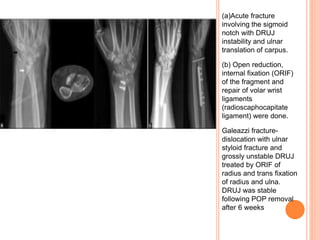

X-RAY OF WRIST WITH DISTAL FOREARM AND HAND

ANTEROPOSTERIOR AND LATERAL VIEWS

(a) Ulnar styloid

with DRUJ

instability

(b) treated by open

reduction and

tension band

fixation. Joint

was stable

following union

of fracture.

(c) Pre- and

postoperative X-

rays of a patient

with fracture of

the ulnar head

(d) treated by

ORIF with

screws

(a)Acute fracture

involving the sigmoid

notch with DRUJ

instability and ulnar

translation of carpus.

(b) Open reduction,

internal fixation (ORIF)

of the fragment and

repair of volar wrist

ligaments

(radioscaphocapitate

ligament) were done.

Galeazzi fracture-

dislocation with ulnar

styloid fracture and

grossly unstable DRUJ

treated by ORIF of

radius and trans fixation

of radius and ulna.

DRUJ was stable

following POP removal

after 6 weeks